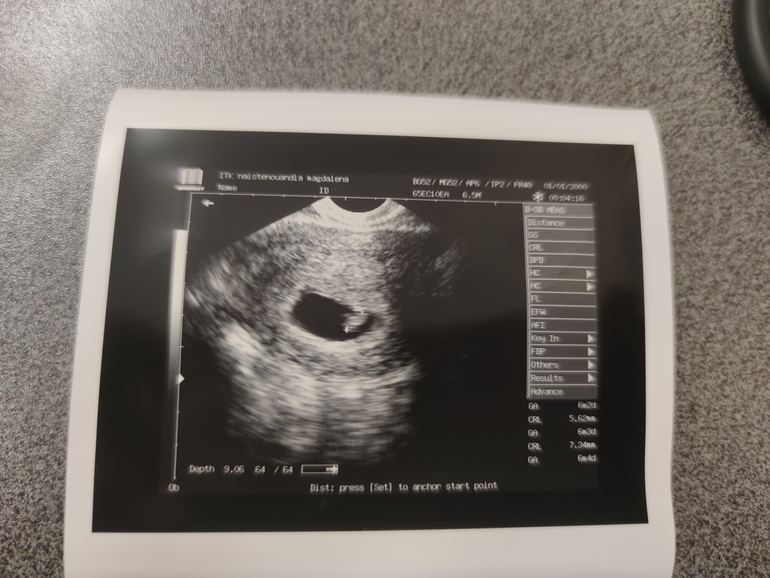

Сходила на узи. Нашли креветку)

КТР 4.1 мм, срок по узи рисуется 6 недель 1 день, ПДР исходя из этого на 24.06.2021. По хгч примерно так и прикидывала) Расхождение с месячными больше 2 недель конечно.

Кстати, что там метод Рамзи говорит? Мальчики слева, девочки справа, или наоборот? 🤣